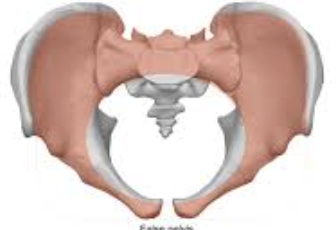

how many bones are in the bony pelvis?

4 bones

what are the bones in the bony pelvis?

sacrum

coccyx

innominate bones (2)

forms part of posterior margin

innominate bones

aka hip bones (consists of ilium, ischium, and pubis)

forms anterior/lateral margin